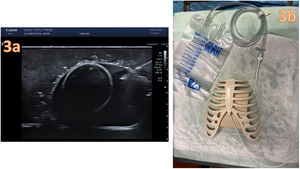

We describe a model that is easy to reproduce, simple, quick, low-fidelity and inexpensive (approximately 10 euro) to provide training on this inherently complicated technique (Figs. 1–3).

Construction of the ultrasound-guided pericardiocentesis model using tofu. (a) Fill a small balloon (5cm diameter) with saline solution and insert it in a larger one (8cm diameter), fill this second balloon with saline using a 50mL syringe. (b) Open a package of firm tofu and make a hole with an ice-cream scoop.